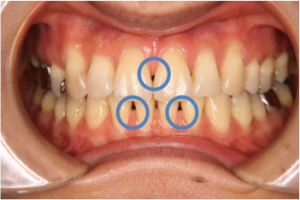

デコボコがあったり、歯が大きく傾斜している状態から適切な位置に歯を移動させると、治療前には無かった歯と歯の間に隙間ができることがあります。(ブラックトライアングル図9、10)

これは元々歯を支える骨がないところに歯が並んでいたために、治療後に歯茎や骨が付いてこない、再生しないためにできる隙間です。これを予防する有効な方法はなく、どうしても治したい場合は治療後に骨や歯茎の移植が必要ですが、そこまでして治す方はめったにいません。

ブラックトライアングルは比較的年齢が高い方が治療をすると生じやすいのですが、補綴物のの作り直し同様10~20代で治療した方にも見られる現象です。